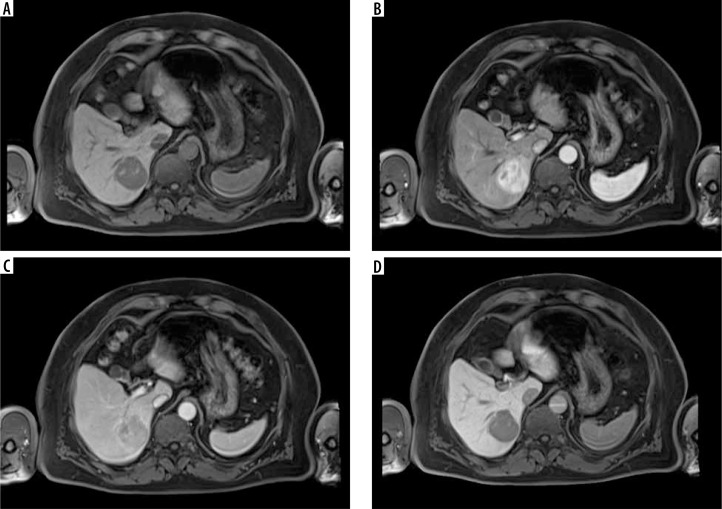

Abstract Image